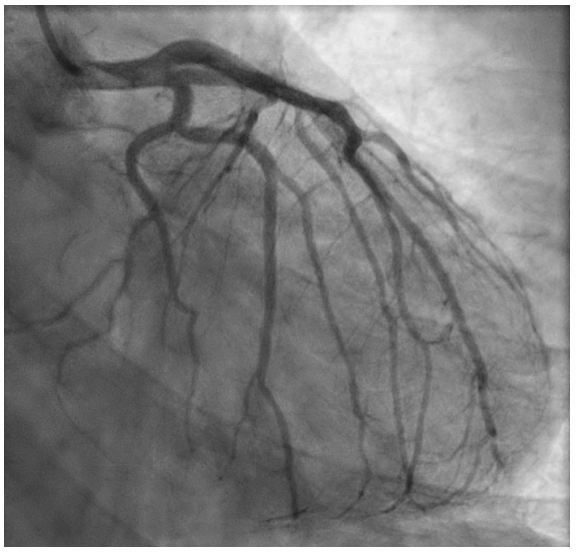

心电图显示:II、III、aVF、V4-V6、I和aVL导联ST段压低,aVR导联ST段抬高伴前间壁q波(图1)。经胸超声心动图显示射血分数保留为55%-60%,无室壁运动异常,中重度二尖瓣反流。左心导管检查显示冠状动脉管腔轻微不规则,而右心导管检查显示充盈压低,心输出量和心脏指数保持正常,右心房压力为0 mmHg,肺毛细血管楔压

为5 mmHg,肺动脉压力为22/7 mmHg,心输出量/心脏指数为4.98/2.83(图2和3)。

图2 冠状动脉造影

右前斜足位(RAO CAU)识图显示左回旋支冠状动脉及左前降支冠状动脉存在轻微管腔不规则。